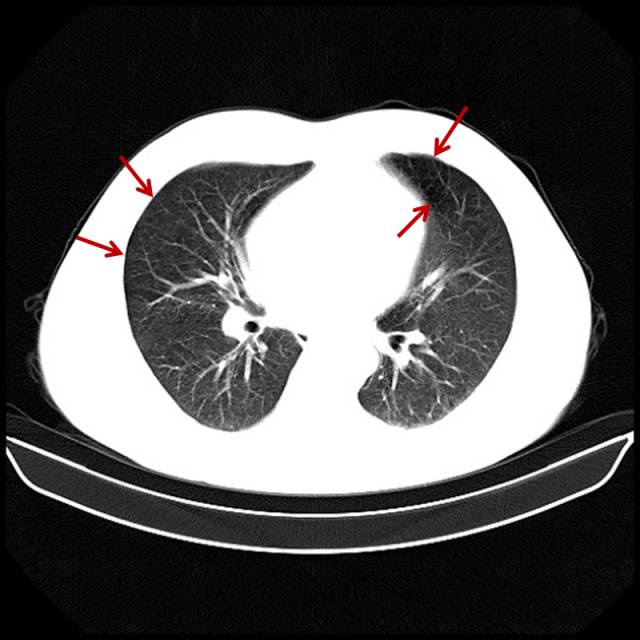

■ 吸烟导致的轻度肺气肿

男,32岁,16岁开始吸烟。